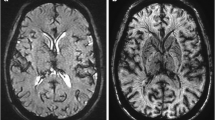

Cross-modal comparison

Figure 5 shows the comparison between f and the DSCCBV in a representative subject. Correlation is observed in gray matter (r = 0.48, p < 10-5) but not in white matter (r = 0.02, p = 0.58). Note that the correlation appears to decrease when DSCCBV is below 0.02 or beyond 0.10. Figure 6 shows the comparison between fD* and ASLCBF in the same subject shown in Fig. 5. Correlation is absent regardless of gray/white matter, presumably due to the large variance (i.e., low precision) in the D* estimate. These observations are highly consistent across subjects (f versus DSCCBV: r = 0.29 – 0.48 in gray matter, -0.02 – 0.05 in white matter; fD* versus ASLCBF: r = -0.01 – 0.12 in gray matter, -0.06 – 0.04 in white matter). Table 1 summarizes the mean and standard deviation of D/f/D*, DSCCBV, and ASLCBF.

Voxel-wise comparison between IVIM-derived blood flow estimate (the product of blood volume fraction f and pseudo-diffusion coefficient D*) and ASL-derived cerebral blood flow (CBFASL). Data is from the same healthy volunteer as shown in Fig. 5. Each circle denotes a voxel

Cross-modal comparison reveals a statistical correlation between f and CBVDSC in gray matter (r = 0.29 – 0.48, p < 10-5), but not in white matter. IVIM model is not robust when CBV is low (CBVDSC < 0.02). The correlation also drops when CBVDSC is beyond 0.10 because these voxels are likely to contain large vessels. Large vessels usually do not comply with the assumption of randomly oriented vasculature. Coherent flow leads to phase accumulation (not signal decay) and in its presence, intravascular diffusion will be attributed to D instead of D*. Taken together, f will be subject to misestimate and low precision. Wirestam et al [21] also reported a correlation between CBVIVIM and CBVDSC (r = 0.563, p < 10-5), but two major differences should be noted between their study and ours. First, their comparison was based on regions of interest, presumably due to limited SNR (36 b-values, but only one measurement). Second, they pooled the regions of interest in gray/white matter and across subjects for correlation analysis. The inherent difference between gray matter and white matter could have inflated and dominated the computed correlation. By contrast, our comparison was on a per-subject and voxel-wise basis, and was performed for gray matter and white matter separately. Our analysis should more correctly reflect the correlation between modalities, and is more applicable for per-measurement assessment. In addition, our data showed no correlation between fD* and CBFASL. This is likely because of the large variance (i.e., low precision) in D* estimate (Figs. 1, 2, and 4b). As mentioned previously, the D* estimate is more SNR-demanding than the f estimate. Based on computer simulation, Pekar et al [24] also pointed out the SNR issue in IVIM imaging, but did not address the relationship between SNR and f/D*.